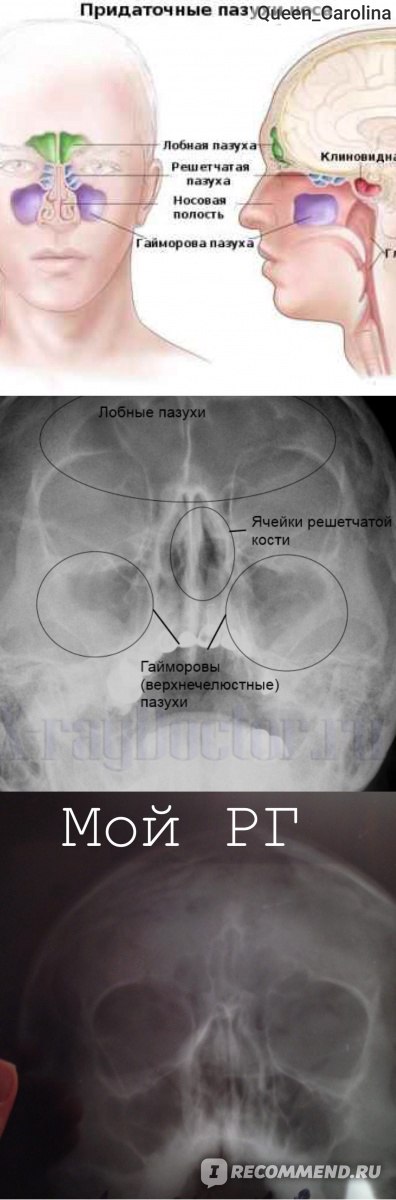

КТ-снимки хронического этмоидита: подробная визуализация

Раздел: Фотодневник открытий